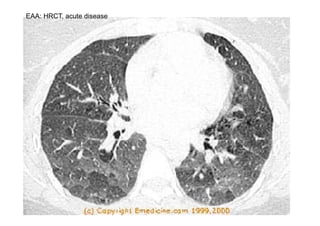

EAA: HRCT, acute disease

EAA: HRCT, chronic disease

• Status • ChestX-ray HRCT • lung function • lab. tests • BAL EAA, clinical findings dyspnea, cyanosis, crepitant rales digital glubbing (chronic form) normal or small nodules/diffuse infiltrates/ ground glass appearance chronic form: pulmonary fibrosis normal or ground glass appearance centrilobular micronodules restriction, diffusing capacity decreases, hypoxemia, obstruction, hyperreactivity rise of sedimentation rate, leukocytosis, neutrophilia marked lymphocytosis, T helper / T supressor cells decreased